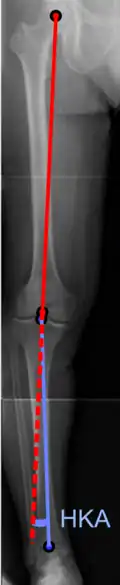

The degree of varus or valgus deformity can be quantified by the hip-knee-ankle angle,[36] which is an angle between the femoral mechanical axis and the center of the ankle joint.[37] It is normally between 1.0° and 1.5° of varus in adults.[38] Normal ranges are different in children.[39]

Hip-knee-ankle angle by age, with 95% prediction interval.[39]